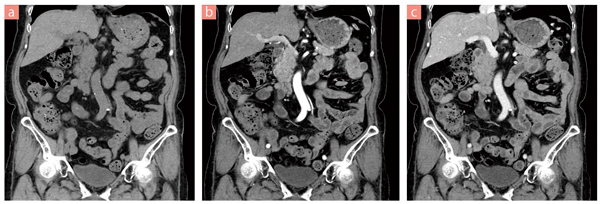

■症例2 腹部精査

a:Plain(管電圧:120kV,管電流:90~150mAs),

b:動脈相(管電圧:120kV,管電流:67~112mAs),

c:門脈相(管電圧:120kV,管電流:67~112mAs)

VolumeEC(患者他の体形に合わせ最適な管電流を設定)にAIDRを連動させることにより,自動的に被ばく低減を考慮した管電流を設定できる。

また,ハイピッチ撮影を行うことで短時間撮影が可能〔HP:111(BP:1.387)〕。